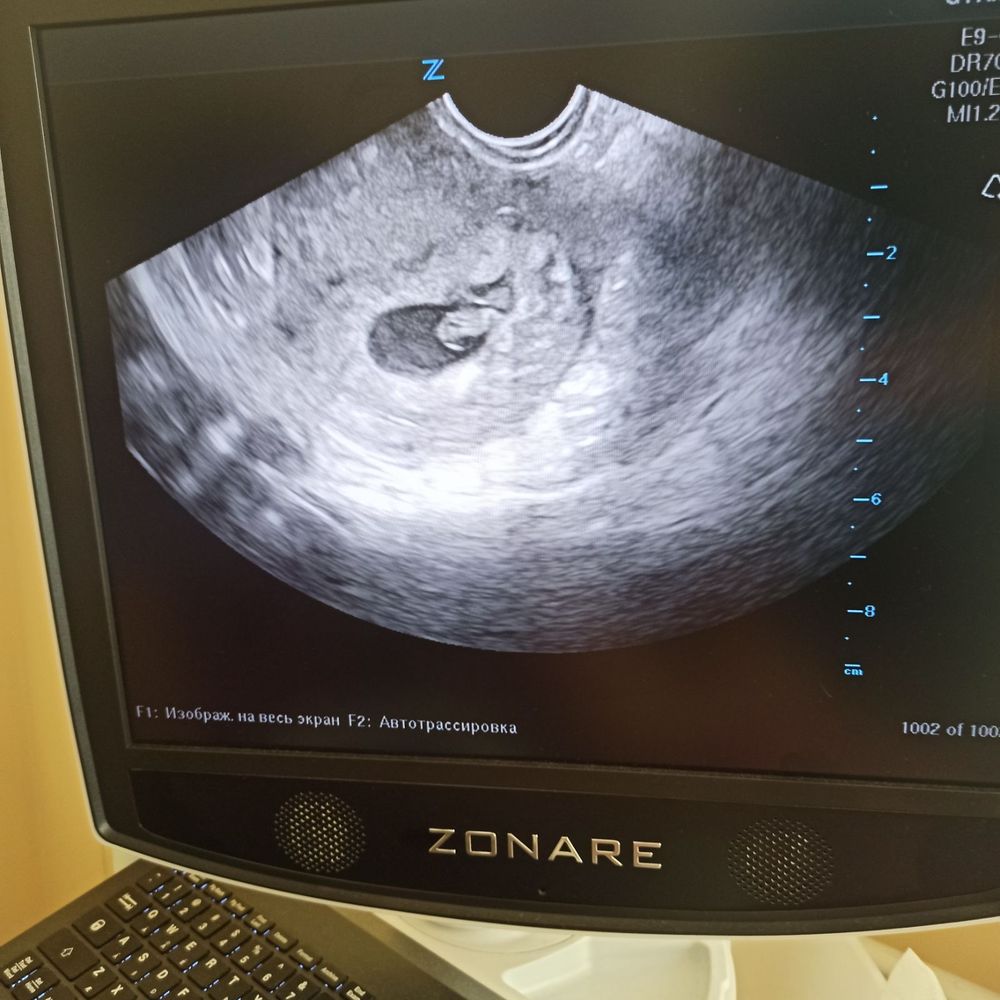

Первый УЗИ у Ре

Сохранение ЭКО-беременностиСегодня была на УЗИ у своей Ре первый раз,до этого делала у себя в городе и было всё нормально,тут ну не много отслойка,ну не много тонус,но ничего страшного не волнуйся,по пьешь таблеточки и всё наладится,вышла с больницы читаю в конце написано угроза перерывания беременности,нормально блин такое писать. Девочки было у кого нибудь такое,отслойка тонус и всё обошлось? Волнуюсь( А ещё КТР 1.1 это нормально для 6-7 недели?